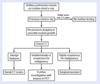

What is the likely diagnosis in a young woman with shortness of breath and the CXR findings below?

Sarcoidosis